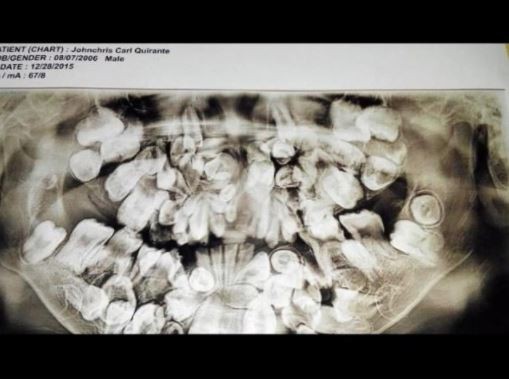

隨著時間的過去,卡爾在5歲時再度去照了X光片,原本50顆的牙齒倍增至150顆,4年後他的牙齒數量已經來到了300顆,多餘大量的牙齒越變越多的情況下,醫生擔心小孩仍小的嘴巴無法承受,於是決定為當時9歲的他動第一次手術,摘除40顆牙齒。